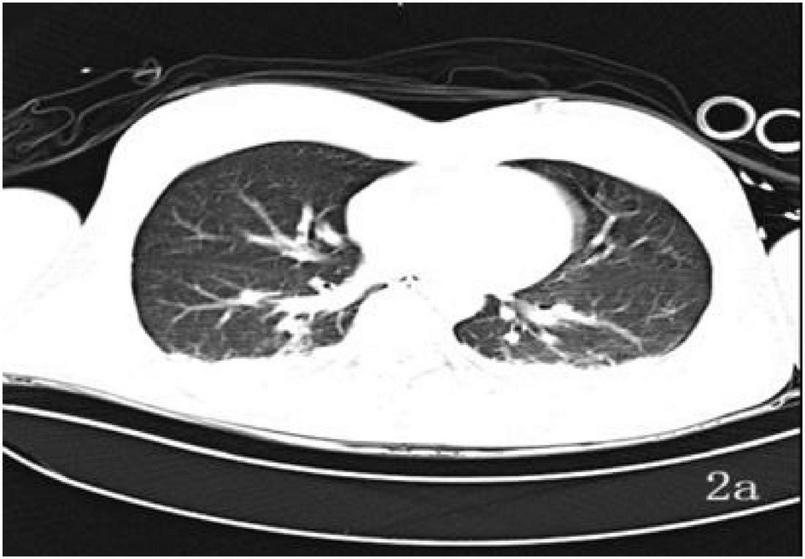

A 39-years-old man was admitted on 13 June 2025 after “loss of consciousness for 30 min following a fall from height with the head hitting the ground.” On arrival he was unresponsive, nauseated, and had projectile vomiting of gastric contents; he was brought to our emergency department by ambulance and admitted to the ICU under the diagnosis of “multiple injuries.” Initial examination: Glasgow Coma Scale (GCS) 4, Injury Severity Score (ISS) 50, temperature 36.5 °C, pulse 88 beats/min, respiratory rate 30 breaths/min, blood pressure 155/86 mmHg. Bloody otorrhea was noted from the right external auditory canal. Cooperation was absent, precluding assessment of tenderness, rebound pain, and limb muscle strength. An occipital laceration with oozing was observed. Initial laboratory evaluation revealed no evidence of severe hepatic or renal dysfunction, while coagulation studies were consistent with trauma-associated coagulopathy, characterized by prolonged clotting times and markedly elevated fibrinolytic markers. Arterial blood gas analysis demonstrated preserved oxygenation with near-normocapnia, accompanied by mild electrolyte disturbance. Neuron-specific enolase was elevated, supporting the diagnosis of severe brain injury. Fecal occult blood testing was positive. Detailed laboratory data at ICU admission are summarized in Supplementary Table 1. Non-contrast brain Computed Tomography (CT) on 13 June (Figure 1a) revealed cerebral contusion, subarachnoid hemorrhage, and skull-base fracture; chest CT (Figure 2a) showed traumatic wet lung.

FIGURE 2

Thoracic CT (a): 13 June–bilateral pulmonary infiltrates and pleural effusions present.

In the treatment of traumatic wet lung, a reduction in bilateral pulmonary exudation shown by chest CT only reflects improvements in lung morphology and cannot directly verify the benefits to brain function; in contrast, cerebral oxygen monitoring can serve as a bridging indicator for “pulmonary ventilation-cerebral oxygen supply.” On June 24th in this case, chest CT indicated improved bilateral pulmonary exudation and reduced pleural effusion. Concurrently, rScO2 increased from 65% at admission to 80%, and PI monitored by TCD remained stable. This confirmed that improved pulmonary ventilation effectively enhanced cerebral oxygen supply, providing direct evidence for “brain function safety” to support weaning from the ventilator and endotracheal extubation on June 23rd. This combined assessment of “morphology (CT) + function” is more effective than a single imaging indicator in guiding decisions at key treatment nodes.